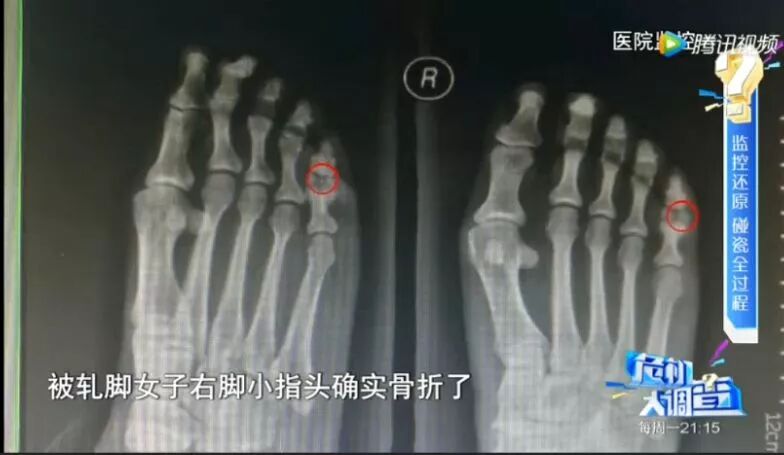

这名碰瓷女子也不是来假的,

送往医院后发现脚趾确实骨折了,

但事后经调查查明,

她是事前用木槌砸断自己的脚趾!![]()